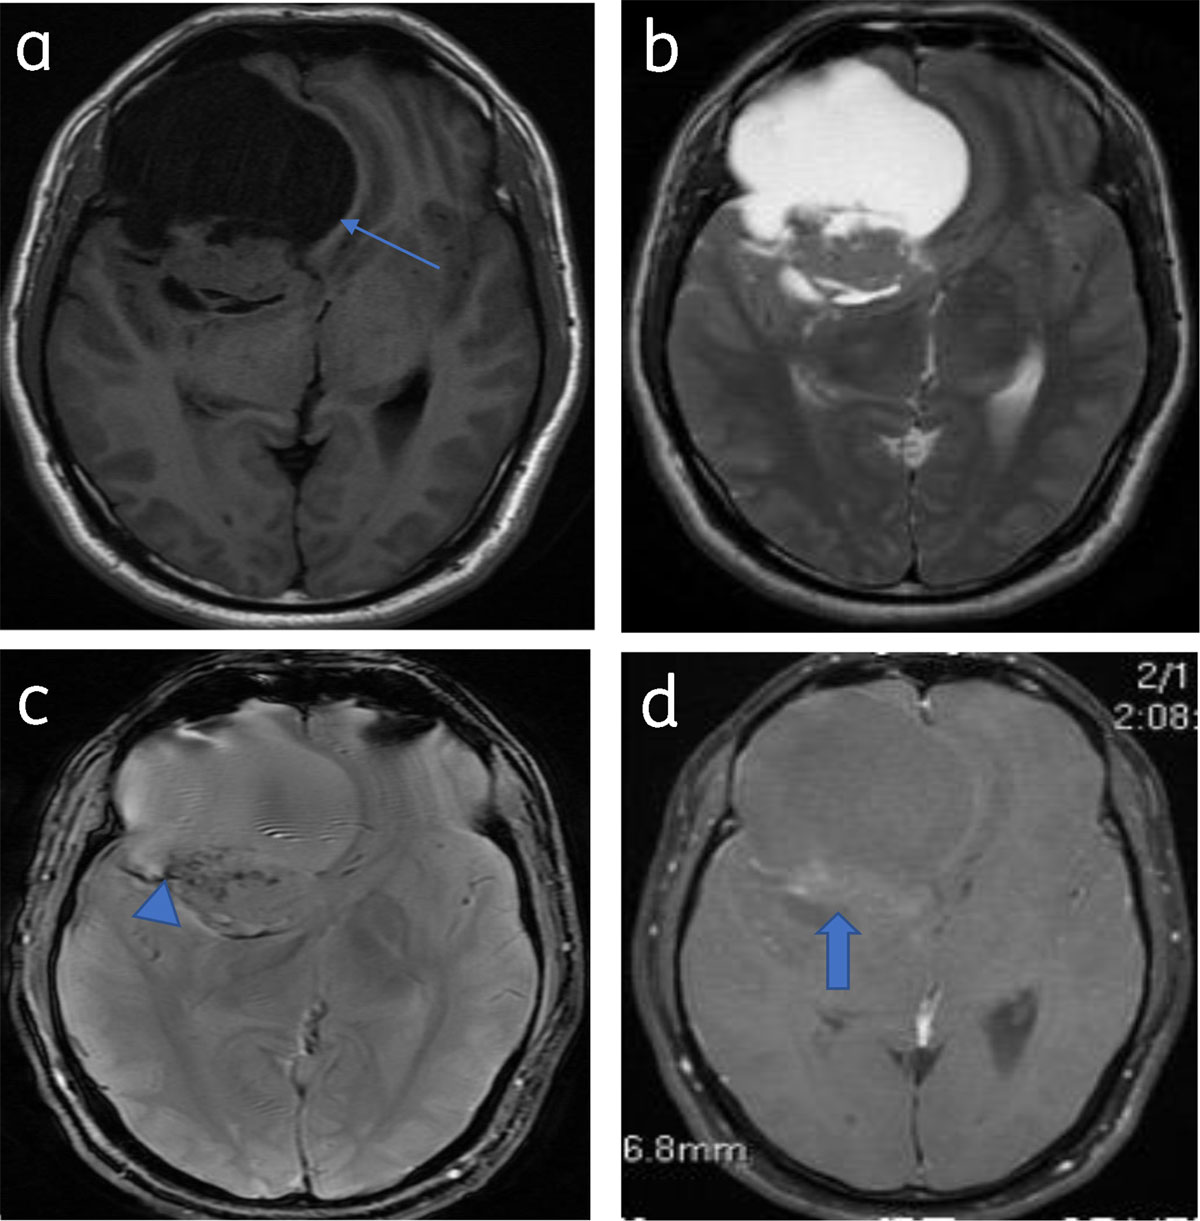

Cystic meningiomas constitute 2 to 4% of intracranial meningiomas. The cystic component may be intra/extratumoral [1] (Figure 14).

Figure 14

Predominantly cystic meningioma: Axial T1WI (a) and T2WI (b) shows right frontal meningioma with subfalcine herniation (arrow). Blooming (calcification) (arrowhead) seen on T2* image (c). Patchy enhancement of solid component (arrow) (d).